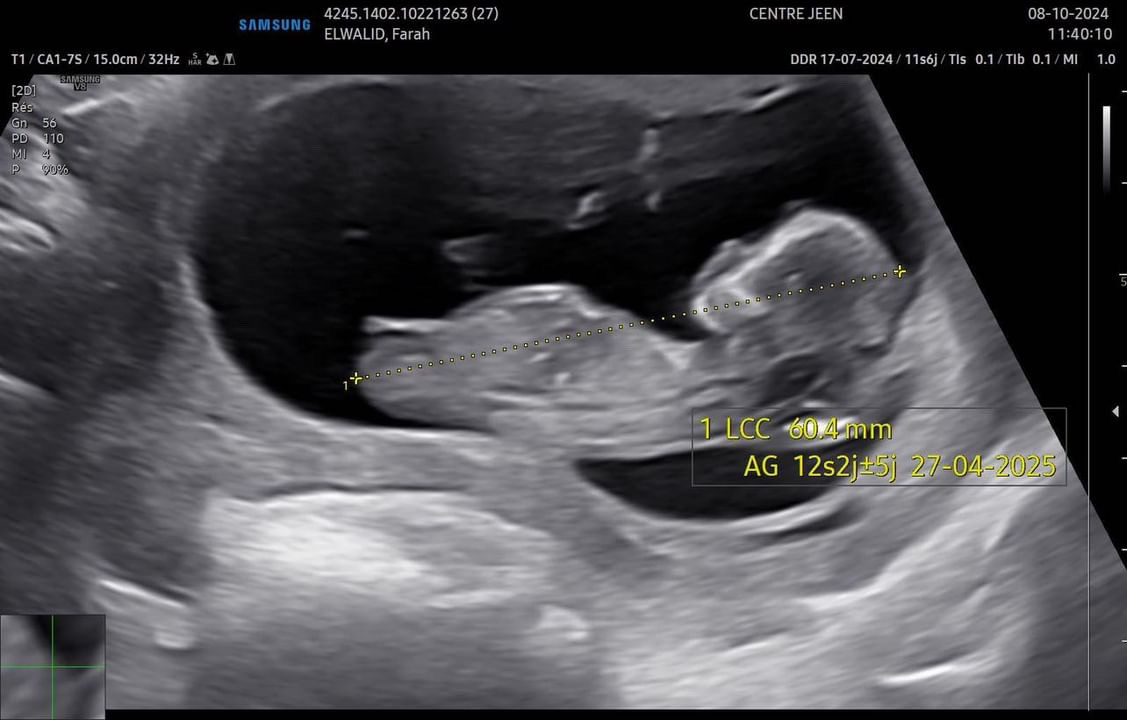

10/2024

Et voici le fruit de notre Amour, le chamboulement de nos vies, notre princesse, Notre Janoush.

27/04/2025

Et maintenant on attend..